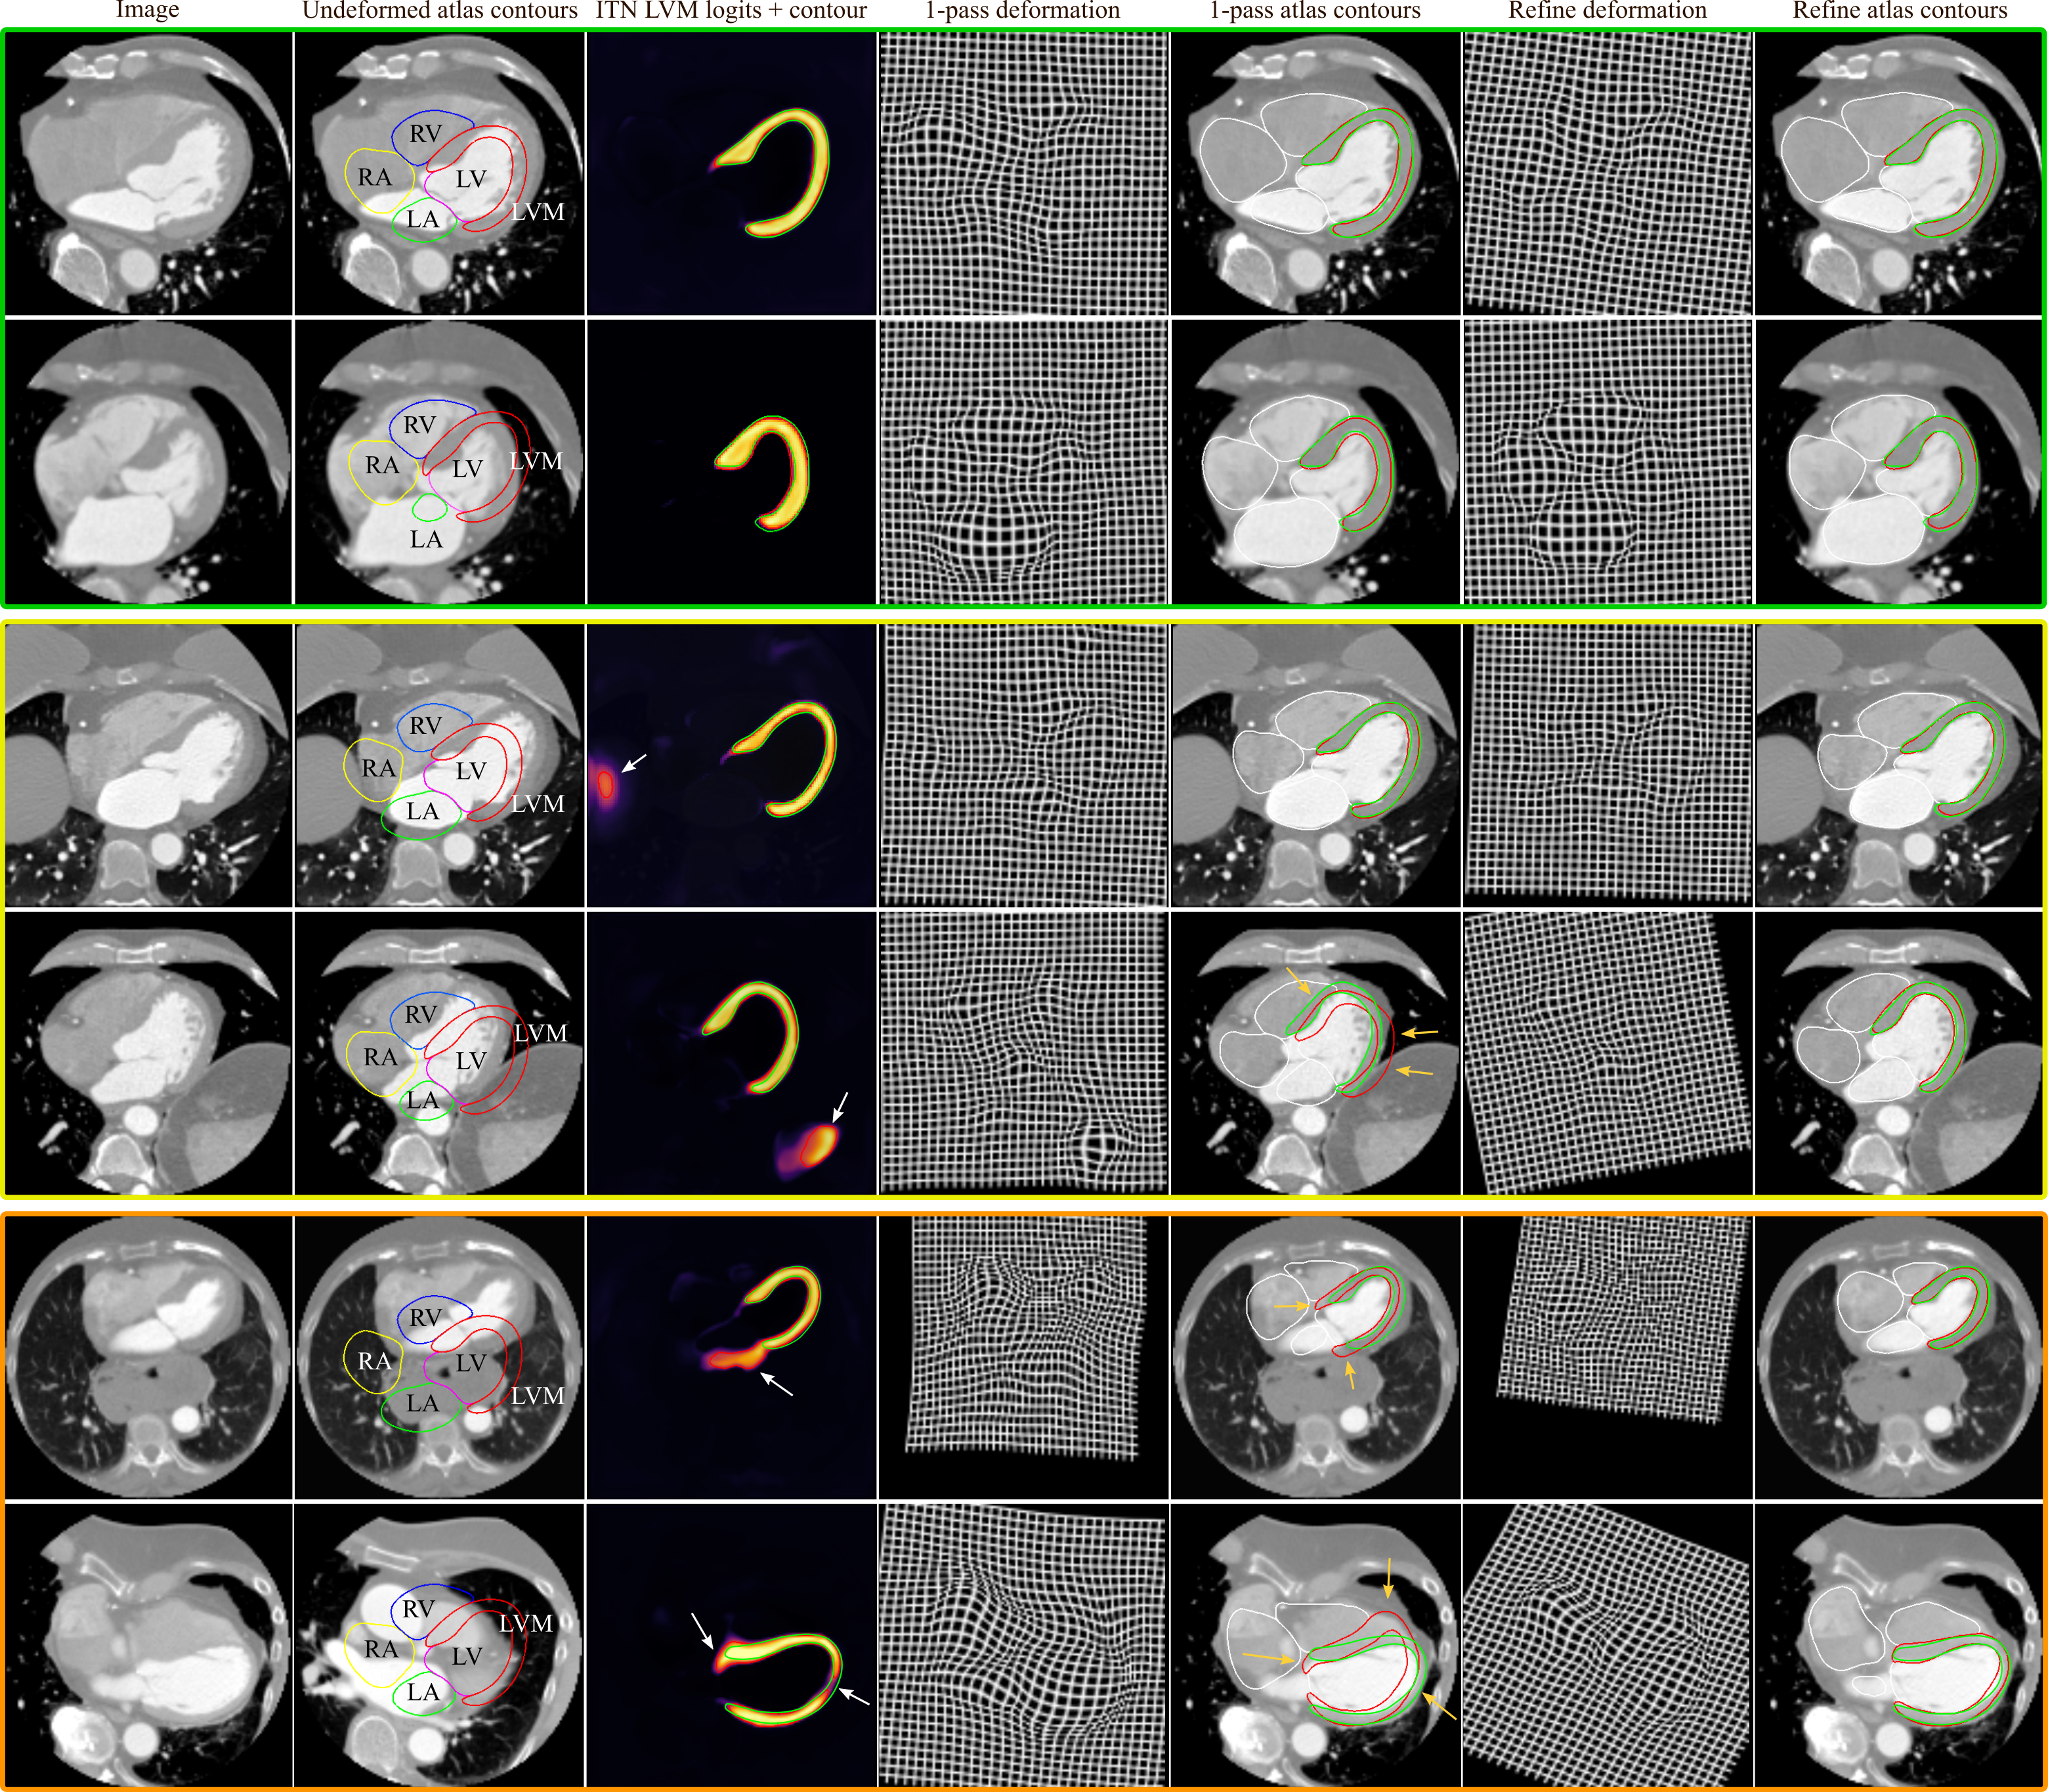

Models were initially trained with no data augmentation, and a significant drop in performance was observed from the ITN to 1-pass DSC (Table 1, left). This highlighted the importance of incorporating spatial augmentations when training the Atlas-ISTN with a limited dataset. The ITN learns both global and local image features, and can primarily rely on local image features to make accurate voxel-wise predictions. The STN performance however depends more heavily on learning global image features, given that the predicted displacement field must operate across the entire image to transform SoI to significantly different orientations, scales and morphological configurations. The bottom two rows of Figure 10 show the outputs of Atlas-ISTN on particularly challenging cases, where significant global and local deformations are required to register the undeformed atlas to the target SoI. The ITN and 1-pass results are inadequate, while the refinement suitably fits the atlas labelmap to the target SoI.

Table 1 shows the results of the U-net and Atlas-ISTN using the high quality 19 case LSA test set, for which labels of all chambers were available. For models trained with no data augmentation, we observe slight improvements of the ITN over the U-net for LVM, LV and RV DSC (, and , respectively), but not for other structures. The 1-pass performance of Atlas-ISTN falls short of the ITN across all metrics for the aforementioned reasons. Refinement produces the best results across almost all metrics, and although DSC improves by a moderate over the ITN, performance on ASD and HD metrics improves significantly. U-net1cc also improves over the U-net in terms of HD and to a lesser extent ASD, but is almost always out-performed by refinement. Fig. 11 shows examples where U-net1cc is unable to correct certain false positive and false negative predictions, while refinement of Atlas-ISTN does.

We observe that U-net1cc improves over the U-net performance both with and without augmentation, and also out-performs the ITN model trained with spatial augmentations. Refinement still produces the best results across both augmentation settings, despite a lower ITN performance compared to the U-net and U-net1cc with augmentation. Additionally, the result of refinement guarantees topology and encourages smoothness of the target structures while U-net1cc does not (see examples in Fig. 11). Statistically significant improvement across all metrics is achieved with refinement compared to all other models.